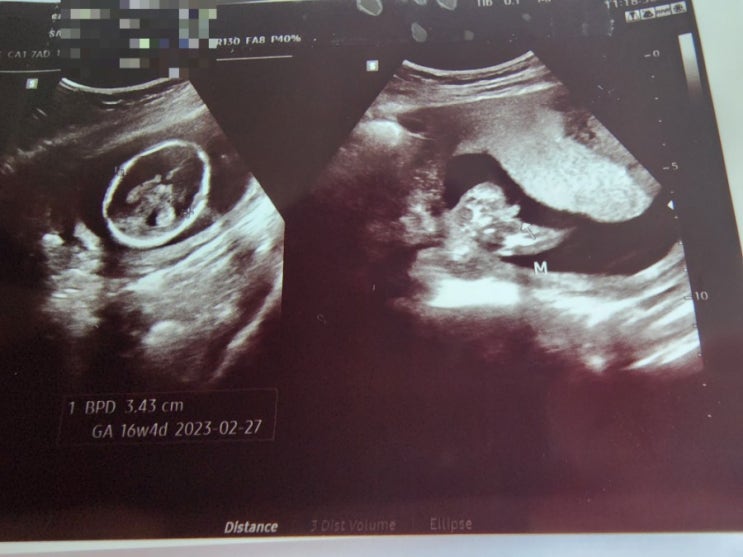

9월16일 (16주1일) 사랑이는 아들이었다.

아무런 느낌이 없으니 불안감이 가끔 생기고 ..약하게 울렁거리기는 계속되어서 그나마 안심하기도 하고 3...

8월29일 13주4일

9월16일 16주인 4주후에 follow-up 이 예정되어 있는데 복직하고 나서 하복부가 피가 안통하는듯한 통증이 ...